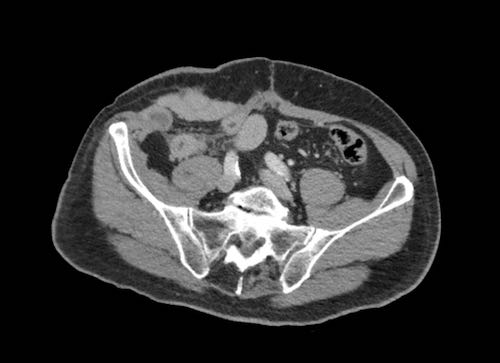

Ca lâm sàng 2

Cuộn qua các lát cắt.

Bạn có thể phát hiện tất cả các tổn thương cấy ghép phúc mạc không?

.jpeg)